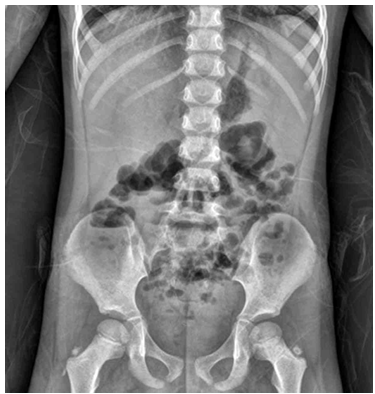

3세 여아가 2일 전부터 토해서 응급실에 왔다. 1일 전부터는 물 같은 설사를 하루 5~7회 정도 했다. 배꼽 주위에 간헐적인 통증이 있다. 체온은 38.5℃이다. 배에 압통과 반동압통은 없다. 혈액검사 결과는 다음과 같다. 복부 X선사진이다. 원인은?

AXR: Bowel gas

• 복부 X선 사진에서 장내 가스 및 air-fluid level이 관찰되지만, 이는 기계적 폐색을 시사하는 심각한 소견이 아니며 바이러스성 위장관염에서 흔히 보이는 비특이적 소견으로 해석된다.